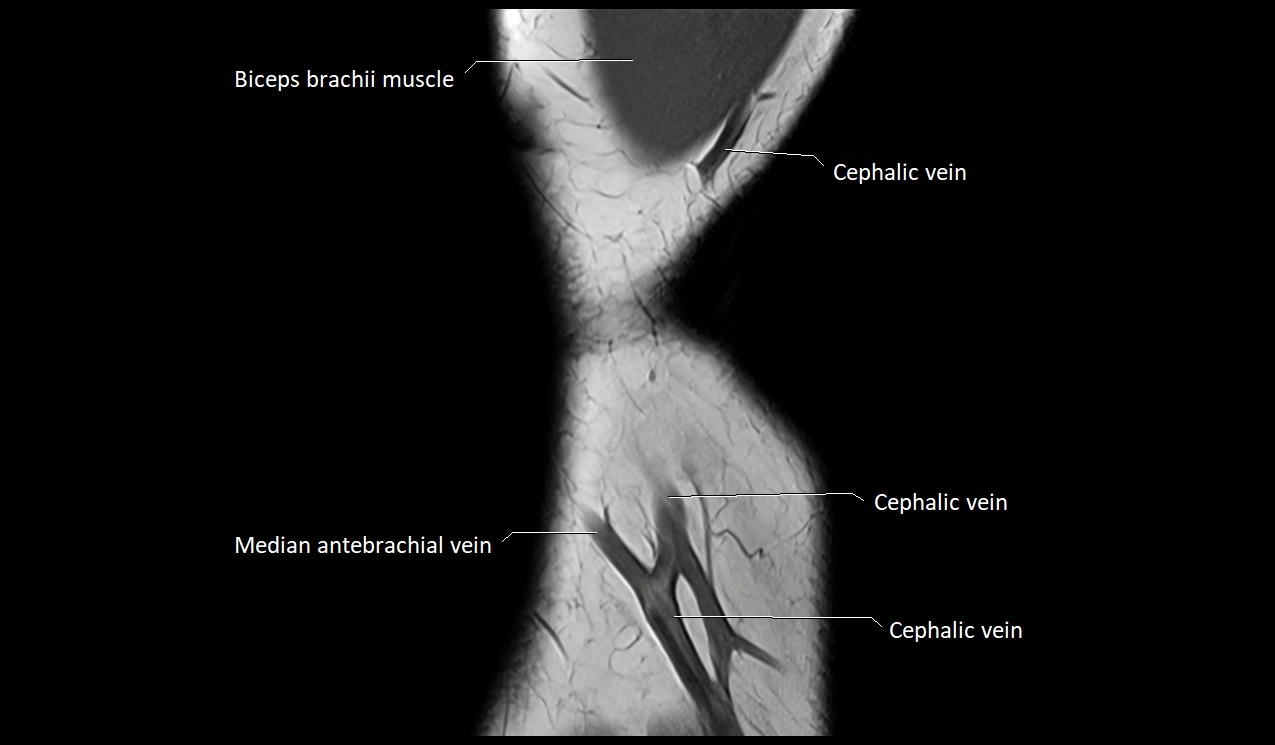

MRI image

image